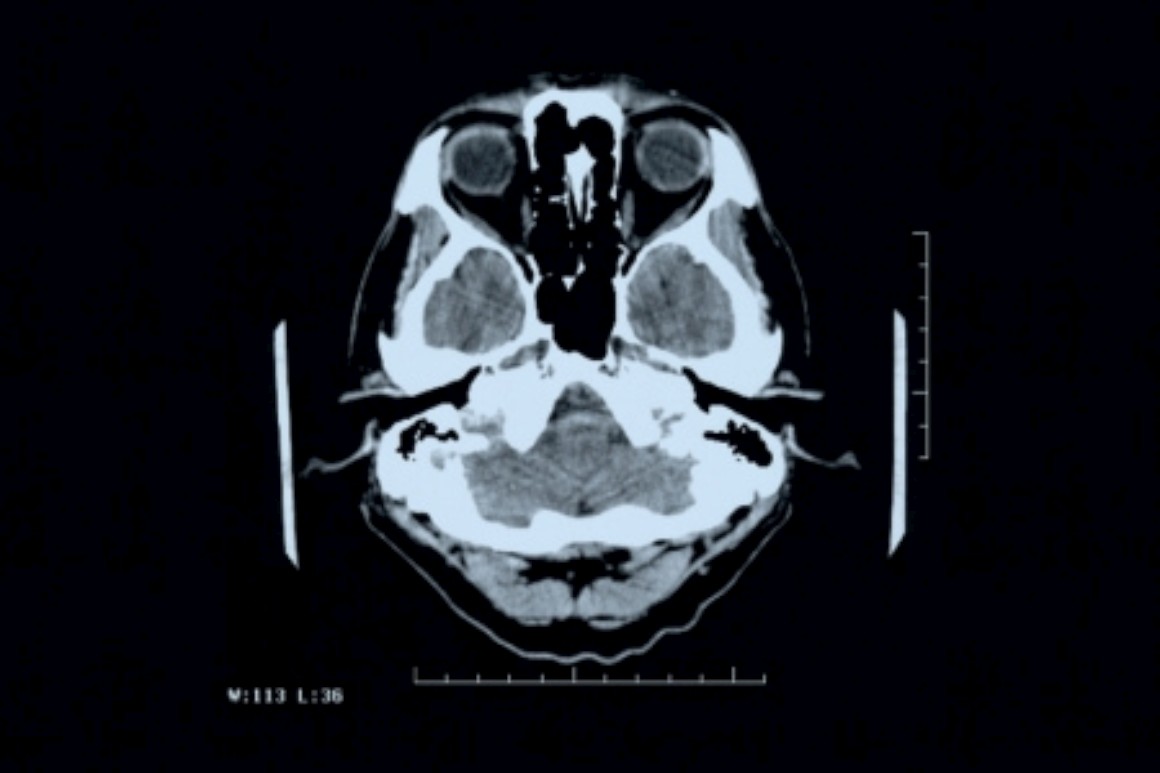

Nos últimos anos tornou-se claro que as mudanças fisiológicas que provocam o declínio cognitivo dos doentes de Alzheimer acontecem muito antes dos primeiros sintomas serem visíveis. A doença, caracterizada a nível neurofisiológico pela deposição de placas da proteína beta-amilóide no cérebro, provoca uma incapacidade cognitiva gradual até os pacientes perderem a memória e a autonomia.